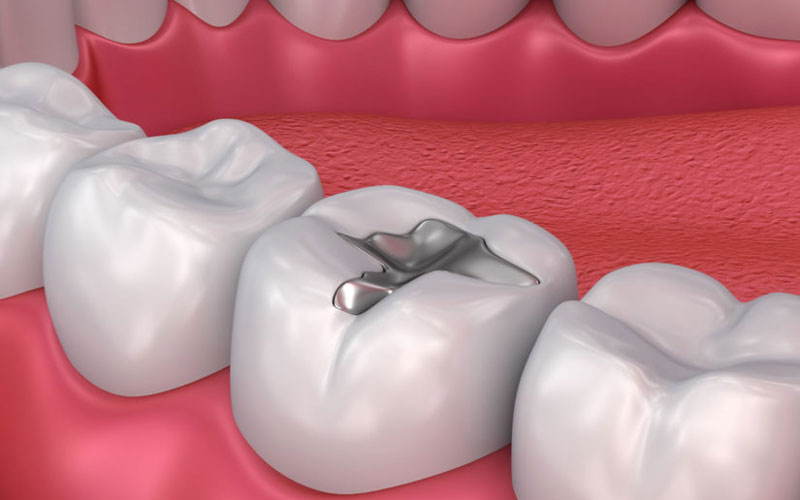

Trám răng thẩm mỹ có thể hiểu đơn giản là kỹ thuật được các bác sĩ nha khoa sử dụng nhằm bổ sung các phần mô răng bị thiếu, mất. Các phần trám bổ sung cần được ghép khớp và đều màu với răng thật nhằm đảm bảo chức năng ăn nhai của răng miệng và tính thẩm mỹ cho bệnh nhân sau khi điều trị.

Hình ảnh trám răng thẩm mỹ đẹp